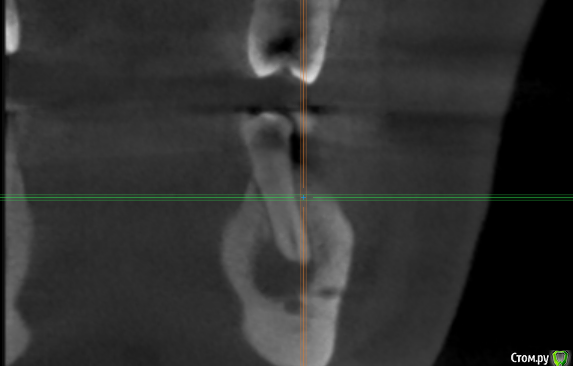

kramer Опубликовано 2 мая, 2018 Поделиться Опубликовано 2 мая, 2018 Коллеги! Помогите, пожалуйста, советом. Пациент обратился с жалобами на зуб 36, характерными для периодонтита (дискомфорт при накусывании, периодические обострения и т.д.). Зубы 35,34 интактные. Сделал КТ, вот что там: Синус-тракт в области 36: Область 35: Мезиально очаг поражения достигает апекса 34 и, видимо, уже частично разрушил компактную пластинку: Если это обычный периодонтит, то 1) почему такие странные очертания очага (или не странные?) 2) с 36 все понятно, но как могли быть поражены 35 и 34? Ссылка на комментарий

kramer Опубликовано 3 мая, 2018 Автор Поделиться Опубликовано 3 мая, 2018 Вы боитесь онко? Когда симптоматика появилась? Когда шестой лечили? Свищ есть или он неактивный сейчас? После лечения шестого симптоматика сохранялась? Есть снимки любые в этой области раньше? Как лимфоузлы? Я считаю, что это хр. гранулирующий периодонтит, согласен с вашим диагнозом. Вопрос только от пятого или от пятого и шестого (моляр недопломбирован).36 лечен давным давно, свищ не активен. Я думаю, периодонтит 36 вследствие неудовлетворительного эндо. Мне неясно, почему поражены 34 и 35. Изначально пациент пришёл с прицельным снимком, на котором видна эта "амеба". Дифдиагноз был между периодонтитом, травматической костной кистой и кератокистой. Вариант 2 отпал после КТ, т.к. компактная пластинка оказалась разрушена у апексов упомянутых зубов. Ссылка на комментарий

Nazim_NV86 Опубликовано 5 мая, 2018 Поделиться Опубликовано 5 мая, 2018 Во первых периодонтит старый. Корни деформированы. Во вторых тип кости такой, поэтому и очаг такой. Об эндо уже поздно говорить. Ссылка на комментарий